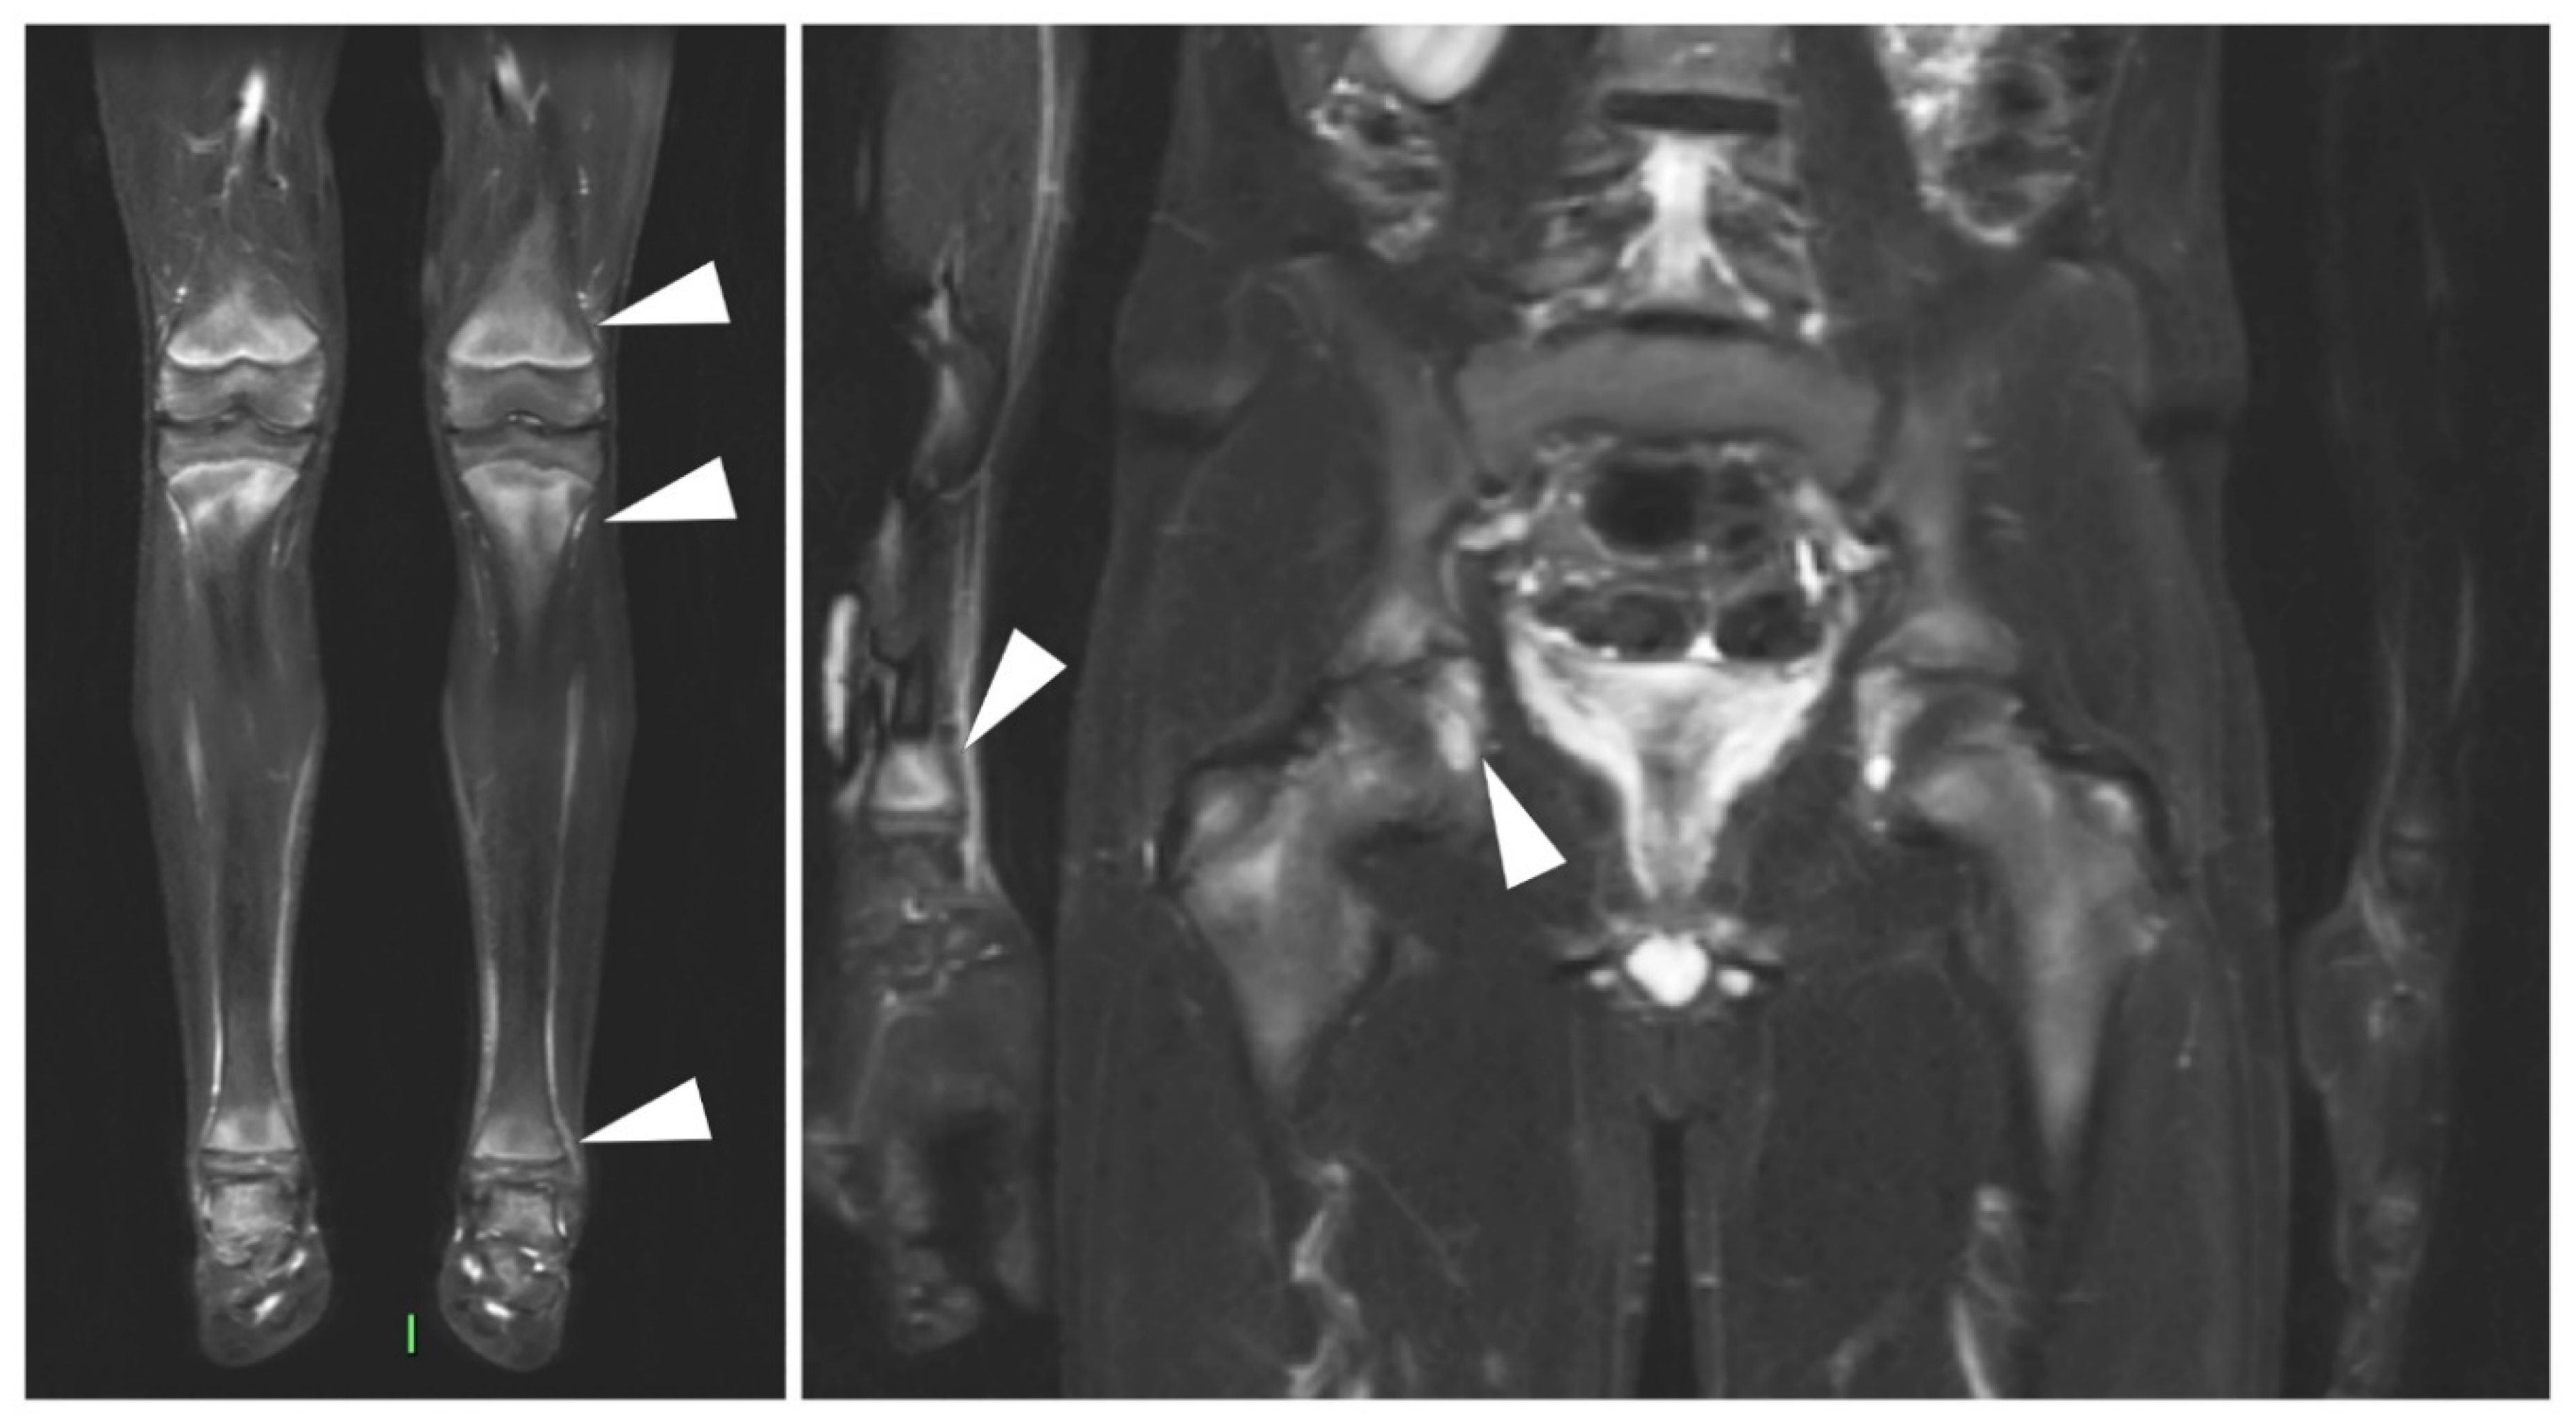

- Eshed, I.; Rosman, Y.; Livneh, A.; Kedem, R.; Langevitz, P.; Lidar, M.; Ben-Zvi, I. Exertional Leg Pain in Familial Mediterranean Fever: A Manifestation of an Underlying Enthesopathy and a Marker of More Severe Disease. Arthritis Rheumatol. 2014, 66, 3221–3226. [Google Scholar] [CrossRef]

- Eshed, I.; Kushnir, T.; Livneh, A.; Langevitz, P.; Ben-Zvi, I.; Konen, E.; Lidar, M. Exertional leg pain as a manifestation of occult spondyloarthropathy in familial Mediterranean fever: An MRI evaluation. Scand. J. Rheumatol. 2012, 41, 482–486. [Google Scholar] [CrossRef]